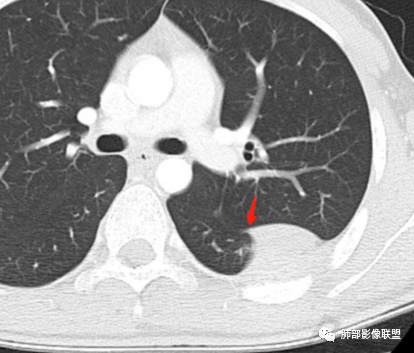

叶裂有变异,但病灶骑跨在叶裂上,外侧宽基底与胸壁相连,呈D子征

胸膜尾

2.左侧叶间裂后缘及胸壁区不规则块影,肺组织一侧边缘光整。密度不甚均匀,未见钙化,不均匀强化,未见明确支气管及肺血管影进入,也未能显示肋间动脉进入。

3.块影有沿胸膜生长蔓延趋势,可见胸膜尾征。胸壁侧边界不清,所经两处肋骨内侧缘骨皮质吸收破坏,局部硬化,边界可分辨。肋骨未见变形膨胀或葱皮样骨膜反应。注意没有胸水。

2.块影沿胸膜生长蔓延,胸膜尾征,肺组织一侧边缘光整,未见支气管及肺血管影进入等也提示病灶位于肺外。

2)生长方式:“铸型”生长;